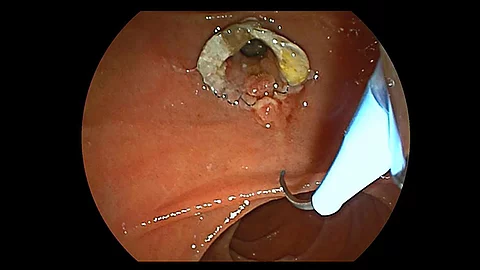

Endoskopisches LehrvideoAPC und Clip bei blutender Angiodysplasie im Magen

In unserem neuen Endoskopie-Video erfahren Sie, wie eine blutende Angiodysplasie im Magen aus einer Kombination mit Argon-Plasma-Koagulation (APC) und Clip behandelt werden kann. Dabei zeigt Ihnen PD Dr. Jochen Weigt vom Uniklinikum Magdeburg, was bei der Durchführung empfehlenswert ist.